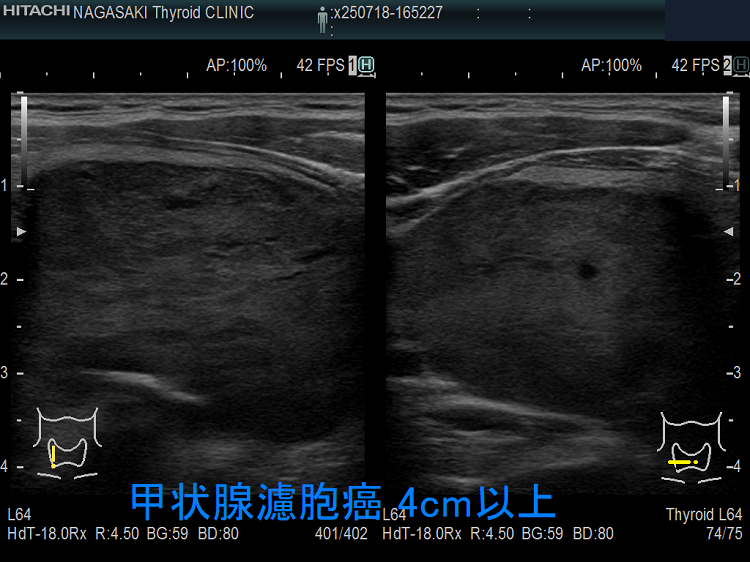

食道を圧迫する巨大甲状腺のう胞腺腫;食道は背側へ圧排され、嚥下障害・誤嚥を来したケース。

喉(のど)の違和感、喉(のど)に引っかかる感じ、嚥下時の違和感があっても、巨大な甲状腺腫瘍や小さくても甲状腺癌の場合を除けば、嚥下障害に至る甲状腺疾患は稀です。

ただし、例外はあって、気管・食道を圧迫する程の

では嚥下障害も起こります。